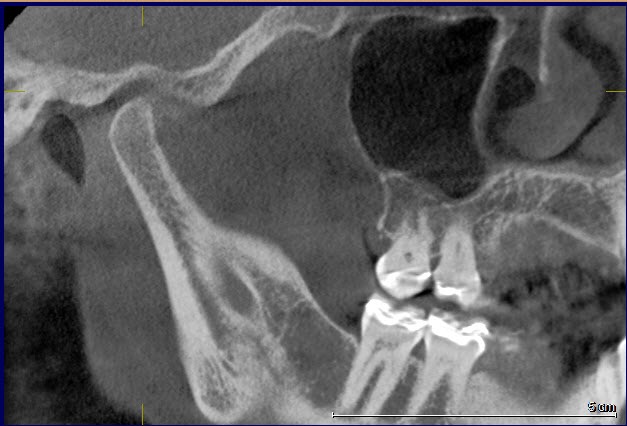

Over 40 million Americans suffer from Myofascial Pain Dysfunction (MPD), a condition that causes headaches and muscular pain. Dr. Klim uses advanced biofunctional diagnostic techniques to decrease painful tension in the head, neck, and shoulder muscles.

Many suffer from Myofascial Pain Dysfunction (MPD) and are not sure of the nature of their condition and how to solve it. You may have heard other terms that describe this condition such as TMJ or TMD. This is short for Temporomandibular Joints. Craniomandibular Dysfunction (CMD) or Temporomandibular Disorder (TMD) are another terms dentist use.